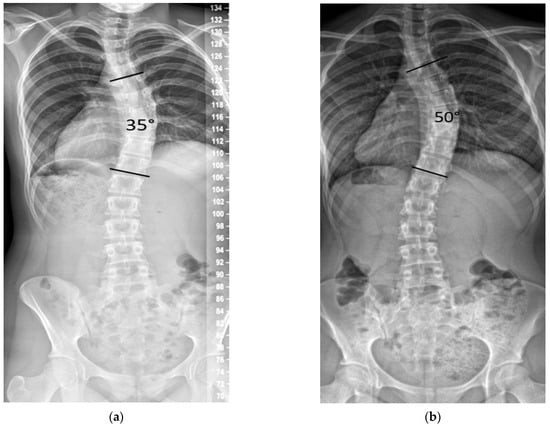

We noted in our practice that some patients with curves between 25° and 45° progressed after documented SM, with some eventually seeking posterior spinal fusion (PSF) due to dissatisfaction with their spinal deformity (Figure 1).

Figure 1.

Example of curve progression after skeletal maturity. (a) Female age 14.6 years, Risser 5, 28 months post-menarche, height 153.7 cm, main curve 35°. (b) Age 17.7 years, height increased by 0.3 cm, and the main curve progressed to 50°.